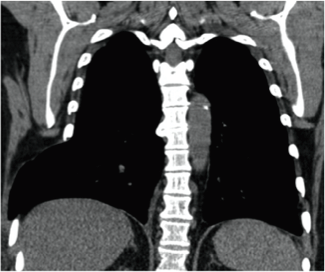

Figura 3.

Hallazgo tomográfico de la hernia pulmonar.

Tomado de: Zia Z, Bashir O, Ramjas GE, Kumaran M, Pollock JG, Pointon K. Intercostal lung hernia: radiographic and MDCT findings. Clin Radiol 2013;68(7):e412-7. http://dx.doi.org/10.1016/j.crad.2012.11.024

La tomografía es la imagen de elección, permite evidenciar la protrusión del pulmón a través de la pared torácica y la adecuada caracterización del contenido herniario, evalúa su tamaño y localización precisa. No existen estudios que evalúen su sensibilidad y especificidad. La administración de contraste intravenoso permite visualizar la vascularización del pulmón herniado para excluir o confirmar la estrangulación del parénquima.27 El estudio con espiración o durante maniobra de valsalva puede demostrar hernias pulmonares aparentemente ocultas y posibles complicaciones asociadas.28,29